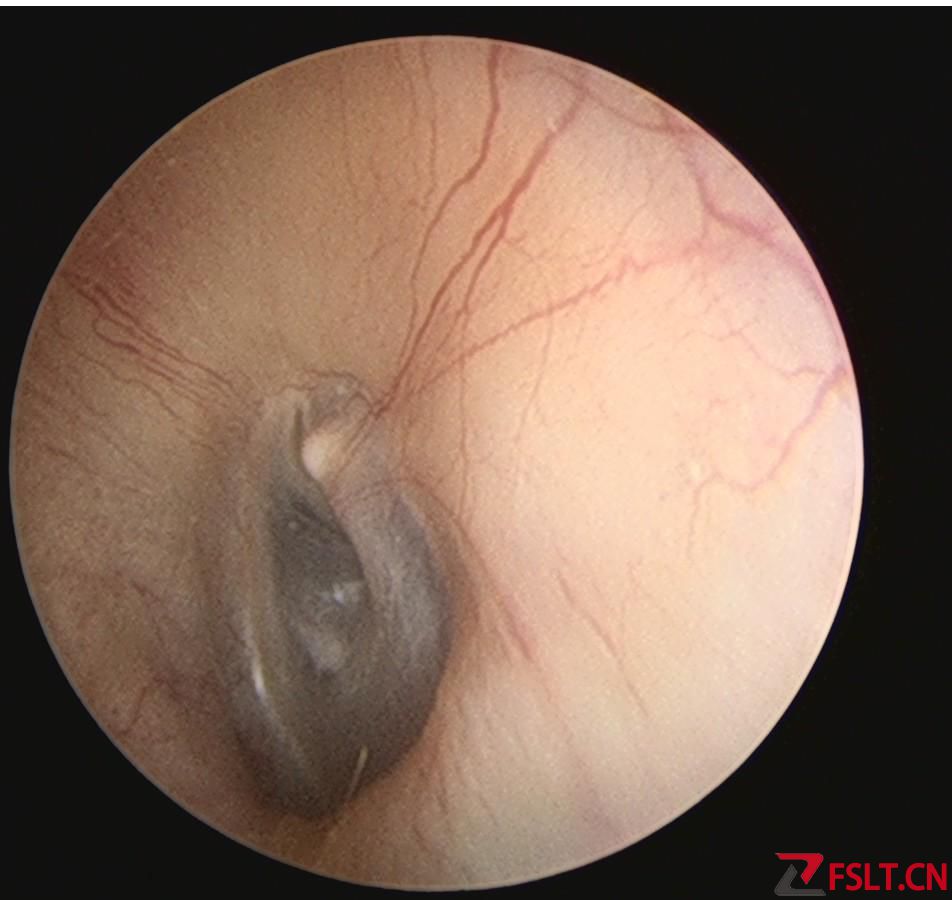

手術(shù)由梅曉峰主任和鄭立崗主任主刀,這次做的是全麻內(nèi)淋巴囊減壓手術(shù),在耳后做切口后暴露乳突骨皮質(zhì),打開乳突腔,暴露后半規(guī)管和內(nèi)淋巴囊,切開內(nèi)淋巴囊放置引流裝置??p合切口并放置負壓引流。整個的手術(shù)用時約2個小時,非常順利。術(shù)后第二天查房患者無明顯的不適,無手術(shù)相關(guān)的并發(fā)癥。自覺耳鳴消失,聽力較術(shù)前稍有提高,無眩暈發(fā)作。